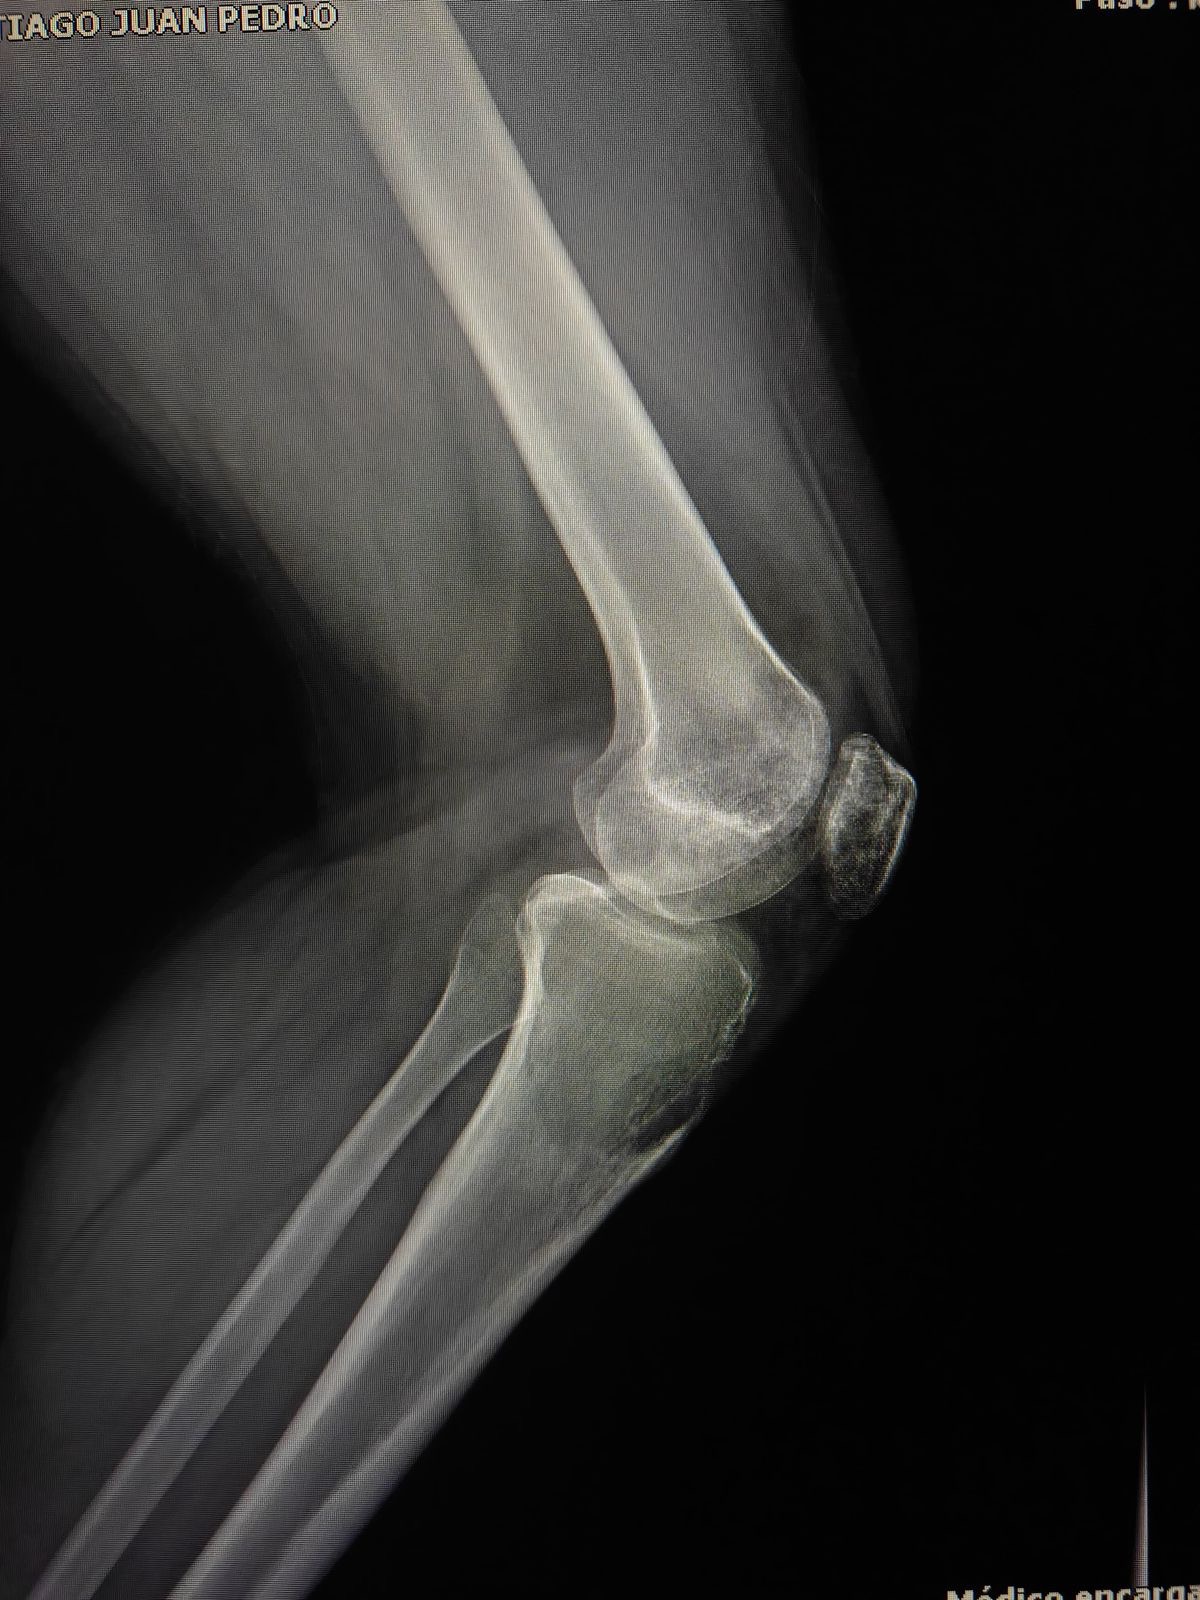

Estoy recaudando fondos para mi novio, quien actualmente tiene un tumor agresivo en la rodilla (tibia). En este momento estamos en espera de los resultados de su biopsia para conocer exactamente el diagnóstico y el tratamiento que seguirá.

salvar su rodilla y su calidad de vida.

Él es una persona joven, fuerte y con muchas ganas de salir adelante, pero el proceso médico implica estudios, tratamientos y posiblemente una cirugía que representan un costo muy alto para nosotros.